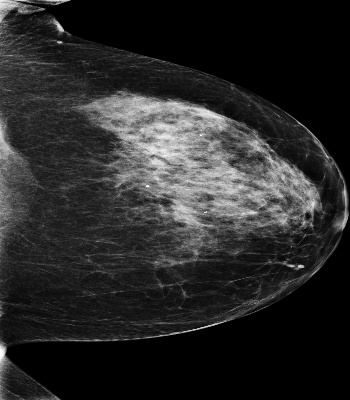

Mammography is used as a standard screening procedure for the potential patients of breast cancer. Over the past decade, it has been shown that deep learning techniques have succeeded in reaching near-human performance in a number of tasks, and its application in mammography is one of the topics that medical researchers most concentrate on. In this work, we propose an end-to-end Curriculum Learning (CL) strategy in task space for classifying the three categories of Full-Field Digital Mammography (FFDM), namely Malignant, Negative, and False recall. Specifically, our method treats this three-class classification as a "harder" task in terms of CL, and create an "easier" sub-task of classifying False recall against the combined group of Negative and Malignant. We introduce a loss scheduler to dynamically weight the contribution of the losses from the two tasks throughout the entire training process. We conduct experiments on an FFDM datasets of 1,709 images using 5-fold cross validation. The results show that our curriculum learning strategy can boost the performance for classifying the three categories of FFDM compared to the baseline strategies for model training.